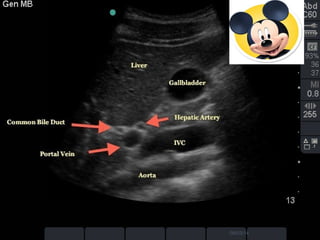

"Mickey Mouse" view of

Portal Triad

  The main hepatic fissure appears as an echogenic

 The complex of the gallbladder, main hepatic fissure,

and portal vein (in the short-axis) has the

appearance of an exclamation point